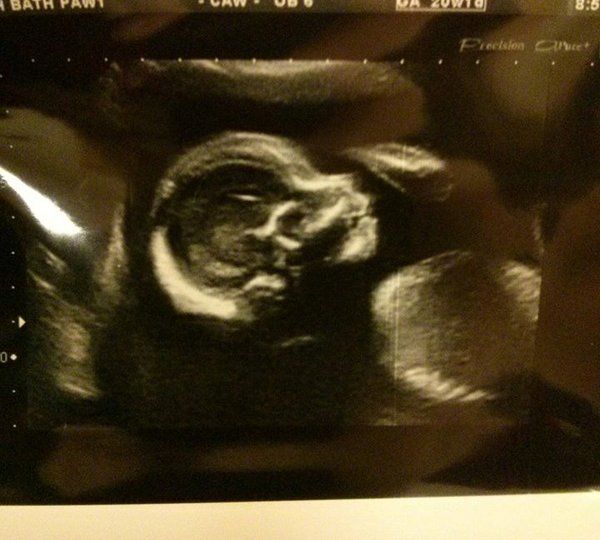

Back from my scan and........ we're having a boy!

Absolutely delighted everything looking & measuring well. No idea what we're going to call him though!

Pug Congratulations on your baby boy :) he's so cute!!